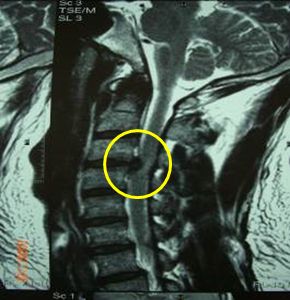

頚椎椎間板ヘルニアのMRI画像